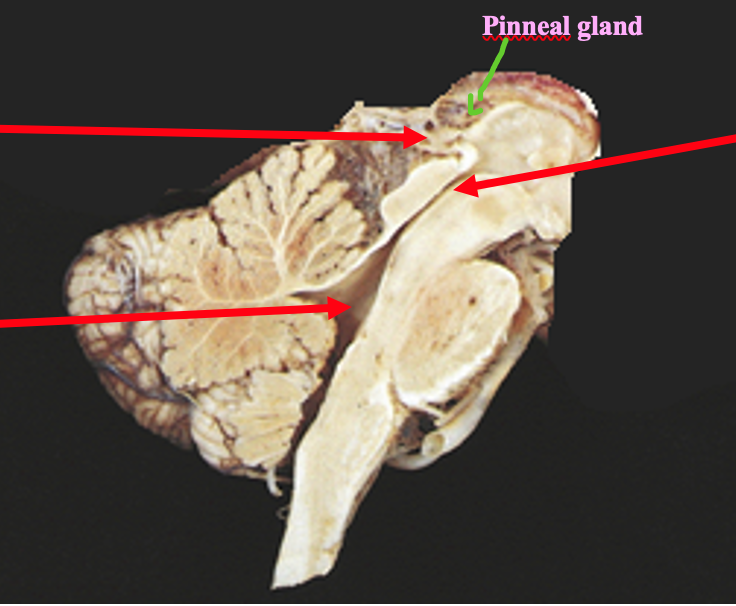

Name this gland

The pinneal gland- part of the epithalamus, posterior to the thalamus